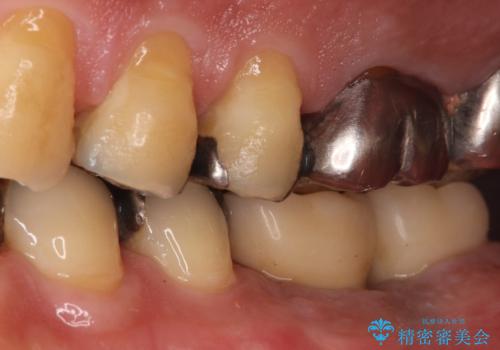

今回の治療では、まず左下6番と7番の欠損部に、骨の状態を考慮しながら慎重に2本のインプラントを埋入しました。インプラント体と骨がしっかりと結合するのを待った後、最短の期間で最終的な被せ物を装着するための精密な型取りを実施。最終的に、周囲の歯と調和した審美性の高いセラミック製の歯を装着しました。

治療期間は約3ヶ月で完了。以前の入れ歯のような煩わしさや動く心配がなくなり、天然歯と変わらない強い力でしっかりと食べ物を噛み砕けるようになり、快適な食生活を取り戻していただけました。